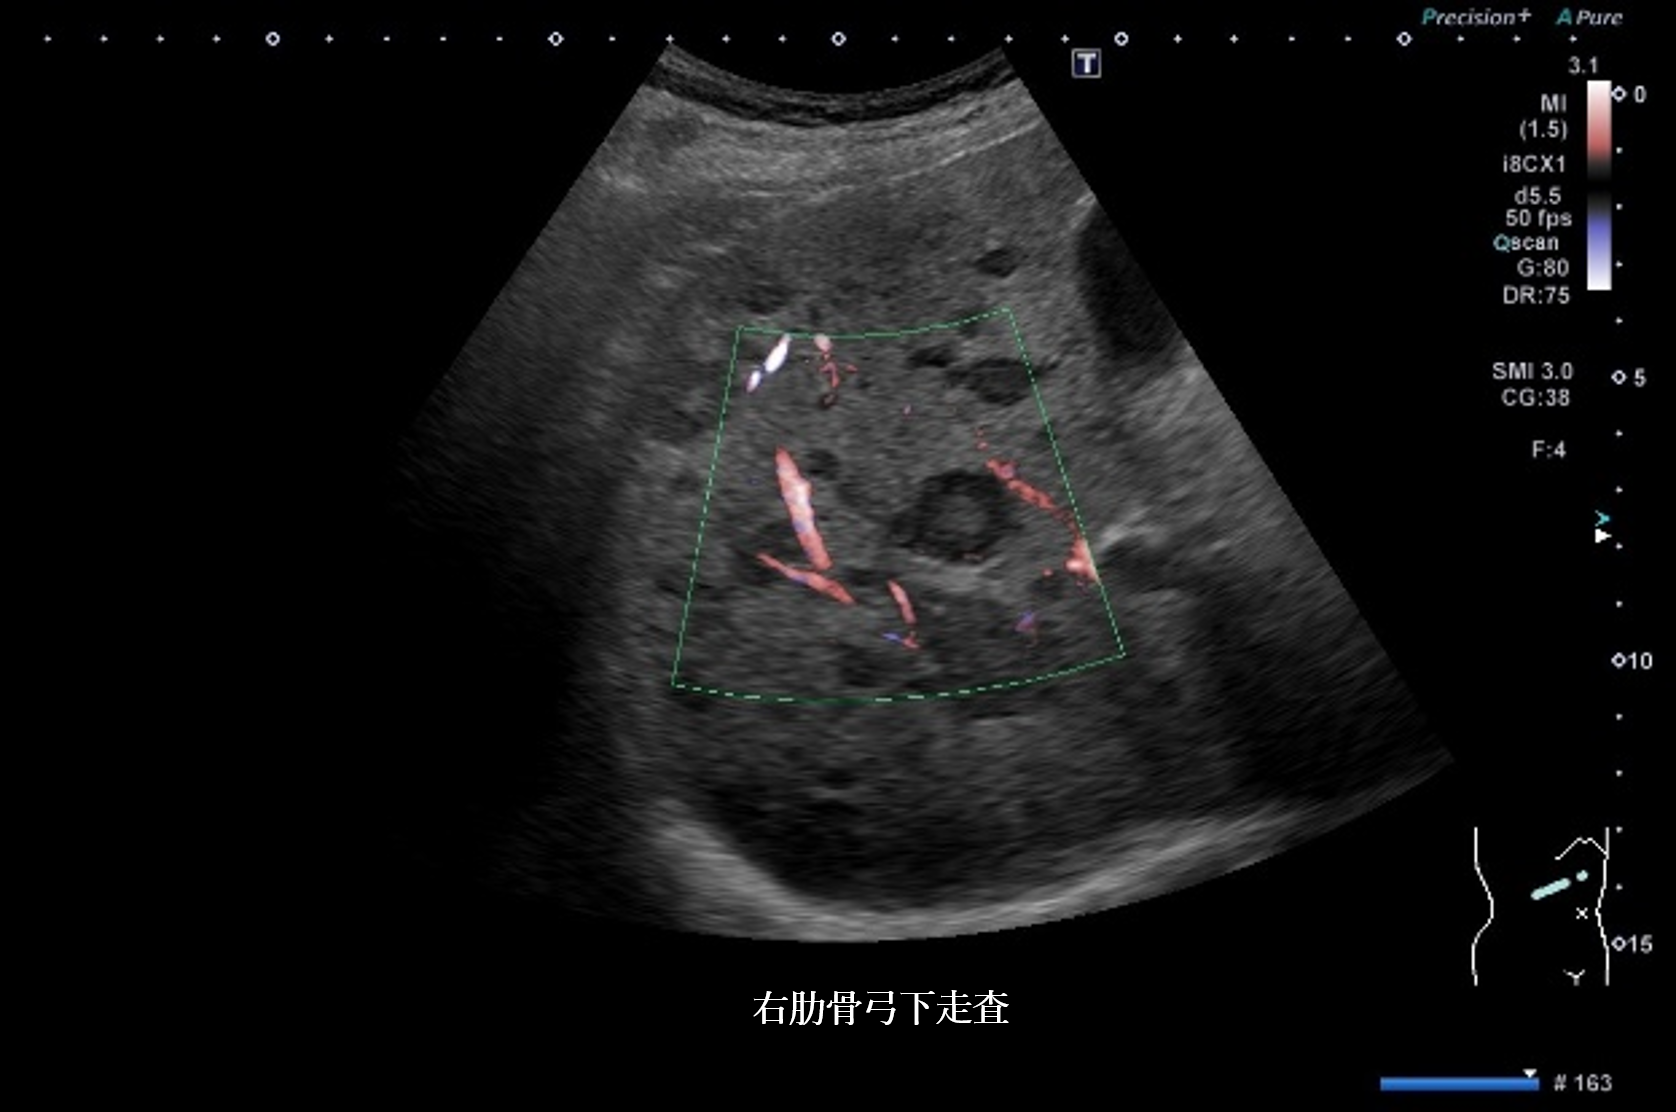

静止画4枚、動画1枚を示す。

腹部超音波1 動画 右側腹部斜走査(No16-17_A)

腹部超音波1 動画(No16-17_A)

腹部超音波画像 画像1(No16-17_1)画像2(No16-17_2)画像3(No16-17_3)画像4(No16-17_4)

静止画および動画から超音波所見と考えられる疾患の組み合わせで正しいものはどれか

① bright loop ― 肝細胞癌

② 後方エコー増強 ― 肝嚢胞

③ nodule in nodule ― 肝細胞癌

④ bull’s eye pattern ― 転移性肝腫瘍

⑤ marginal strong echo ― 肝血管腫